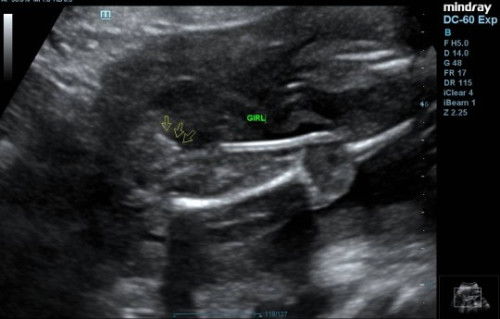

Betul ke kalau selepas melahirkan anak selagi kita tak period makna nya okay kalau kita tak pakai perancang . #ingintahu #firsttimemom saya pakai perancang depo tpi dh stop ingat nak tukar ke iucd. Boleh tk share pengalaman yg pernah pakai iucd